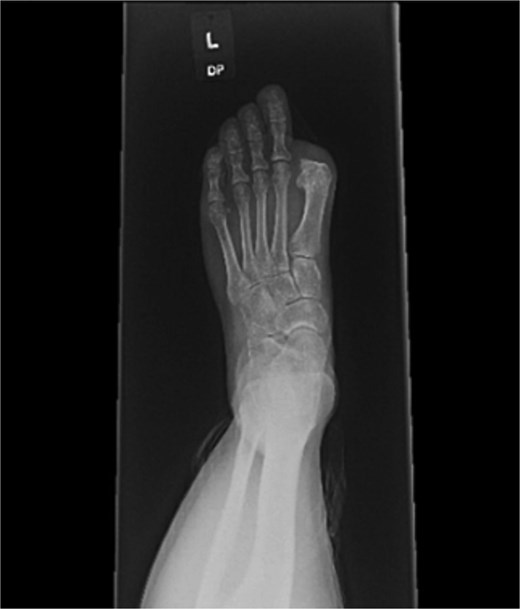

A 44-year-old active woman, with a body mass index of 19.7, presented with symptomatic left hallux rigidus. Her past medical history included only celiac disease; she had no history of smoking, diabetes, peripheral vascular disease, or other conventional vascular risk factors. Her sole medication was spironolactone. She underwent standard first MTP arthrodesis with articular surface preparation, demineralized bone matrix, and fixation using two headless compression screws (Fig. 1). A tourniquet was applied just above the ankle; however, the exact duration was not available because the procedure was performed at an outside hospital. She received perioperative cefazolin prophylaxis.

Postoperative radiograph showing first metatarsophalangeal joint arthrodesis with two headless compression screws.